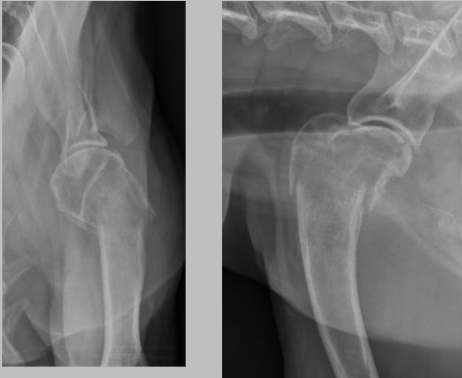

what kind of bone lysis is this and why? is this an aggressive or non aggressive bone lesion?

A

geographic: can see the well defined margins and you can easily tell the lytic bone from the adjacent normal bone. this is a subchondral bone cyst

a non aggressive bone lesion

12

Q

what is the pathology seen here?

a sunchondral bone cyst, can see a little circle of radiolucency in the subchondral bone on the medial chondyle